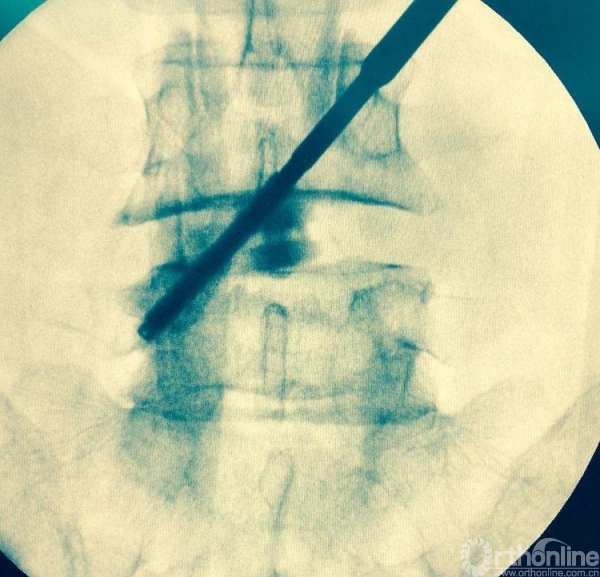

术前透视标记出棘突椎板关节突关节、椎弓根、横突复合体螺钉进钉路线的正位透视片

正位观察透视,判断是否处理至边缘

正侧位透视观察滑脱是否复位、融合器及植骨的位置